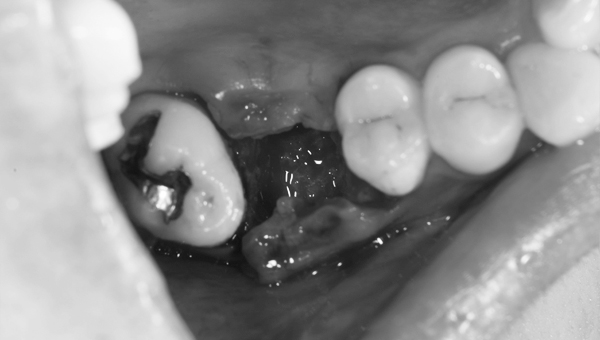

歯が大きく欠けた

歯ぐきが治癒した

説明:

右上の歯が大きく欠けています。黒く虫歯になっているのがわかります。移植を計画しましたので、歯ぐきがしっかり治癒するのを(1ヶ月)待ちました。